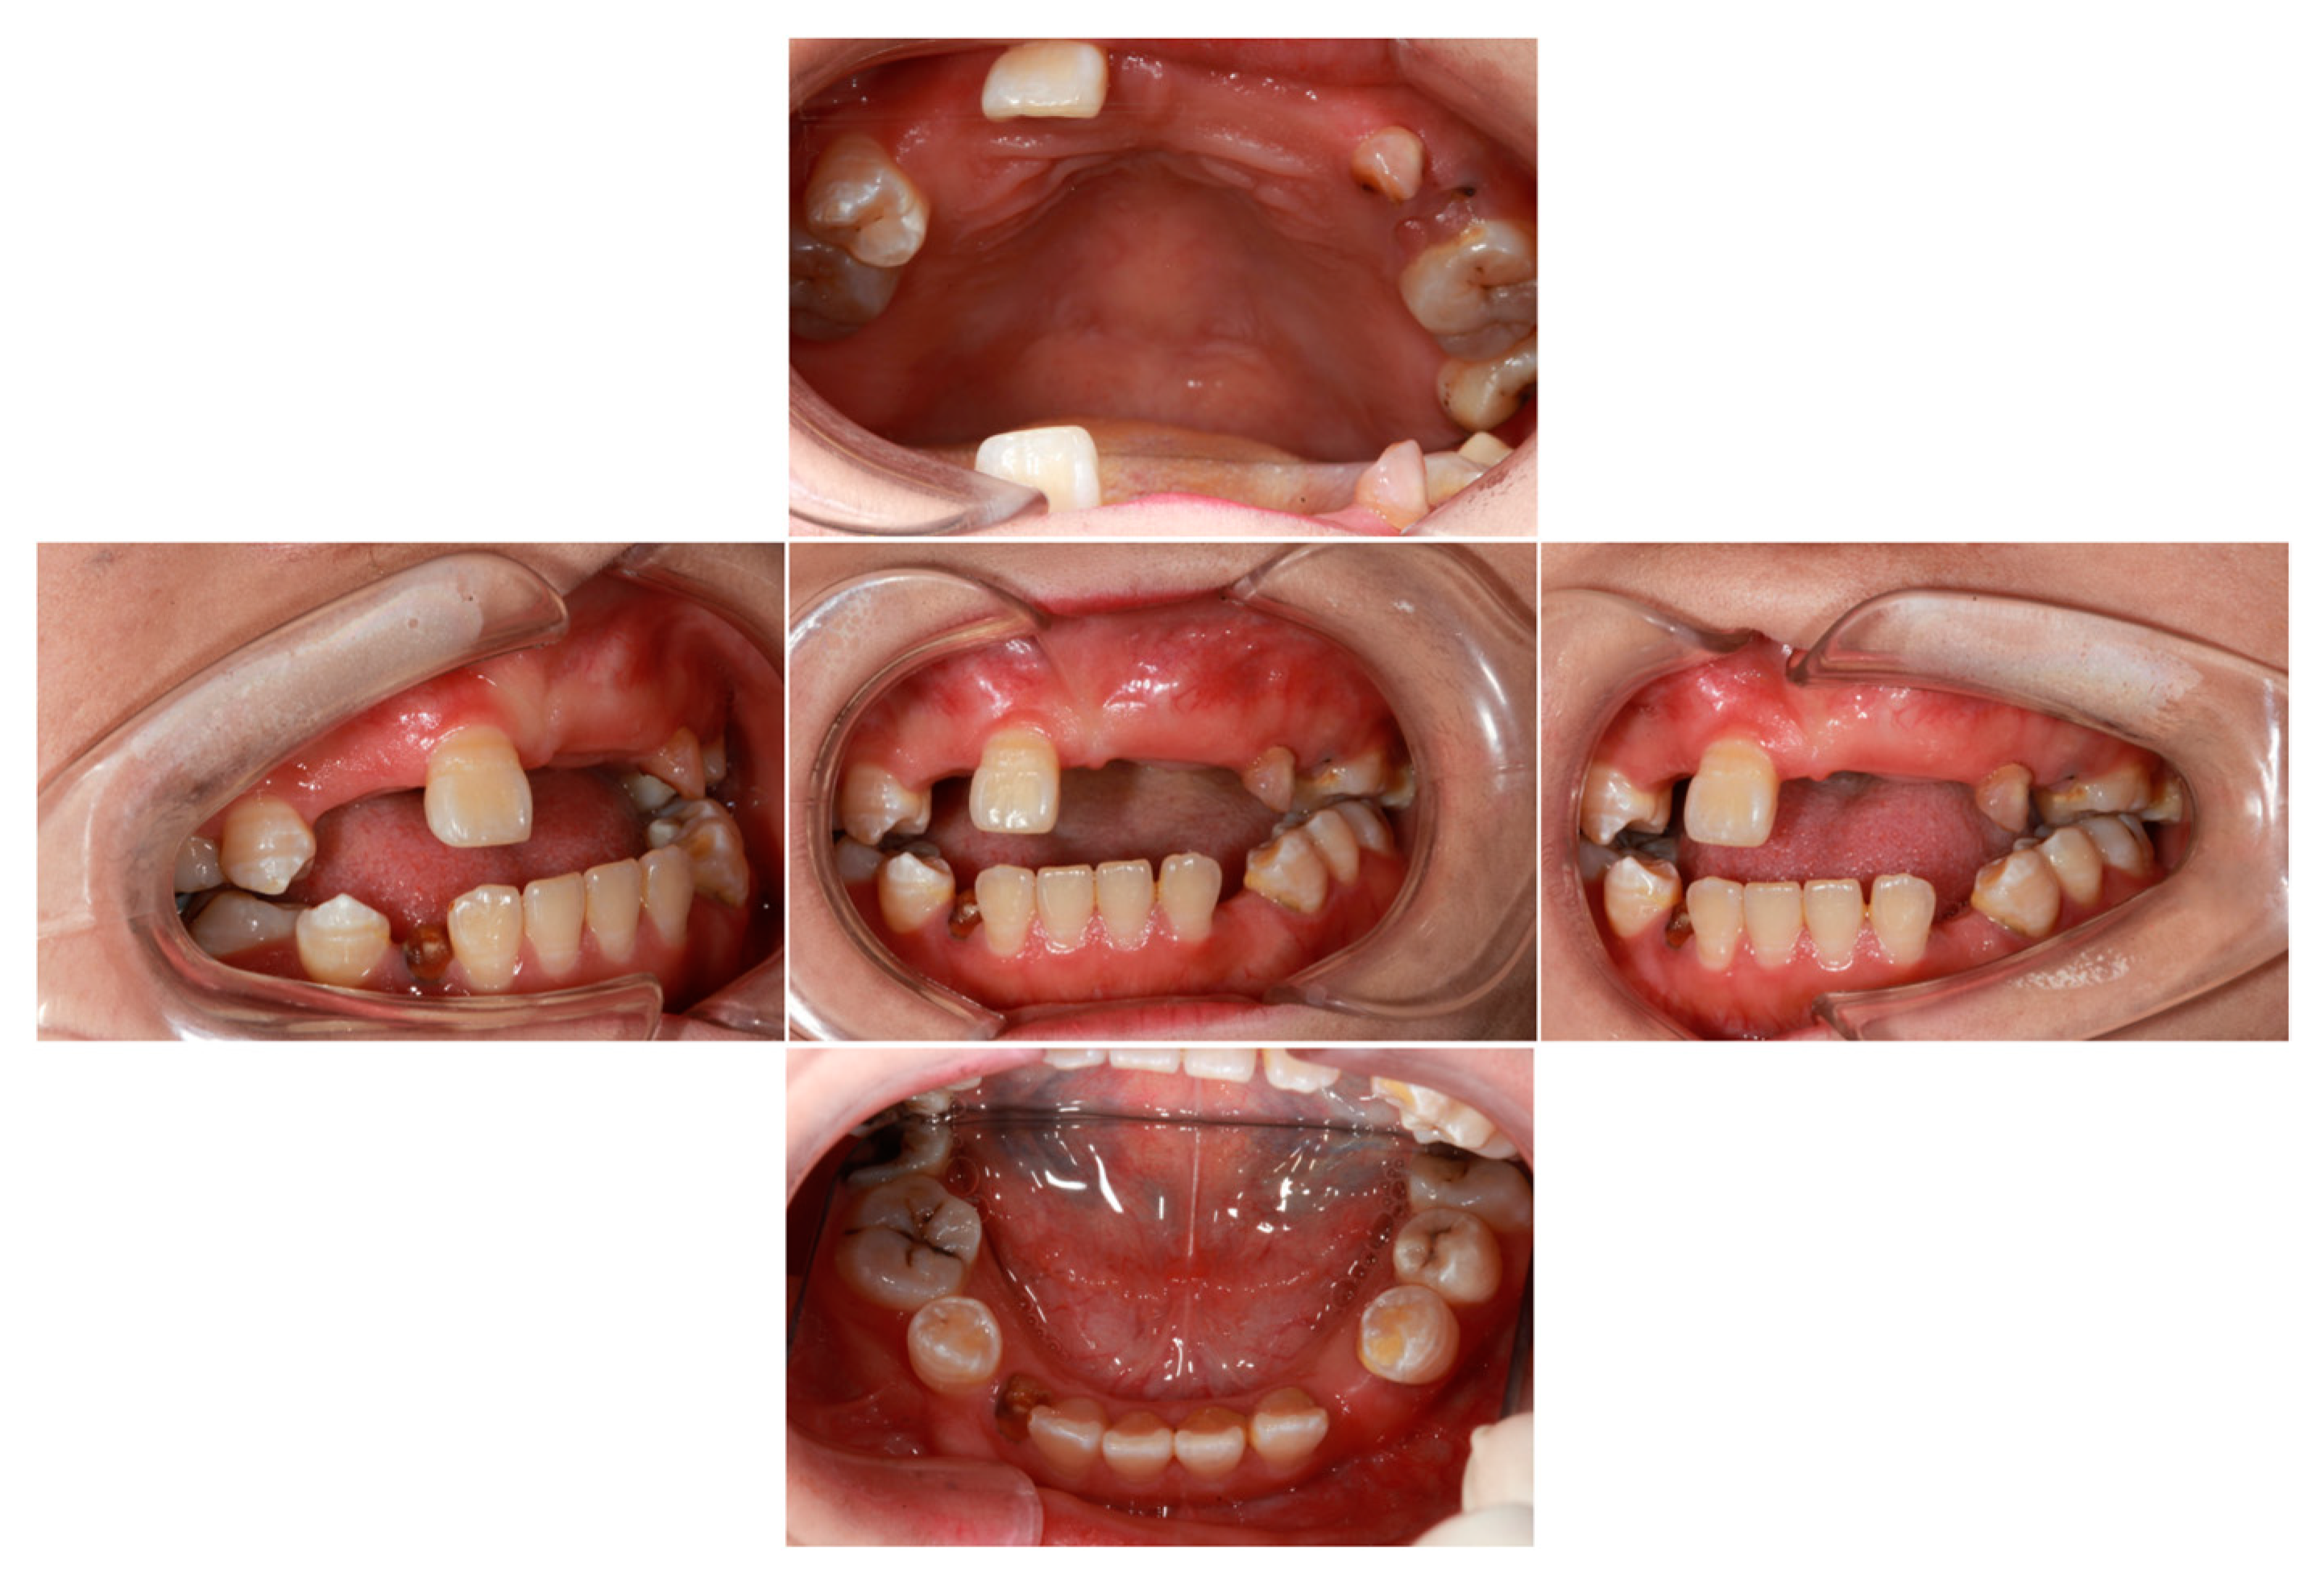

The results of the general physical examination indicated that the proband’s vital signs were stable, with her respiratory rate, blood pressure, body temperature, and other parameters all falling within the normal range. The oral examination revealed the persistent retention of the upper left deciduous canine and the residual root of the lower right deciduous canine. Additionally, a residual root was identified in the upper left second premolar. Enamel hypoplasia was observed in the upper right second premolar, lower right first premolar, and lower left first premolar. Moreover, the upper right lateral incisor, canine, first premolar, second molar, upper left central incisor, lateral incisor, canine, first premolar, lower left canine, lower right canine, and lower right second premolar were not detectable during the clinical examination (as depicted in Figure 1). The proband also presented with suboptimal oral hygiene, a pronounced anterior open bite, and a mild midfacial retrusion.

Figure 1.

Oral examination of the proband revealed multiple unerupted teeth. The left upper deciduous canine and the right lower deciduous canine (root remnant) were retained. Additionally, enamel hypoplasia was observed in the right upper second premolar, right lower first premolar, and left lower first premolar.